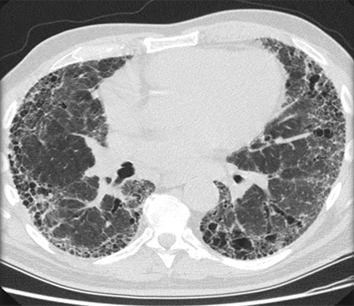

Exploración por TC de tórax en la que se muestra fibrosis pulmonar idiopática

De la colección personal del Dr J. C. Munson, Center for Clinical Epidemiology and Biostatistics, University of Pennsylvania School of Medicine